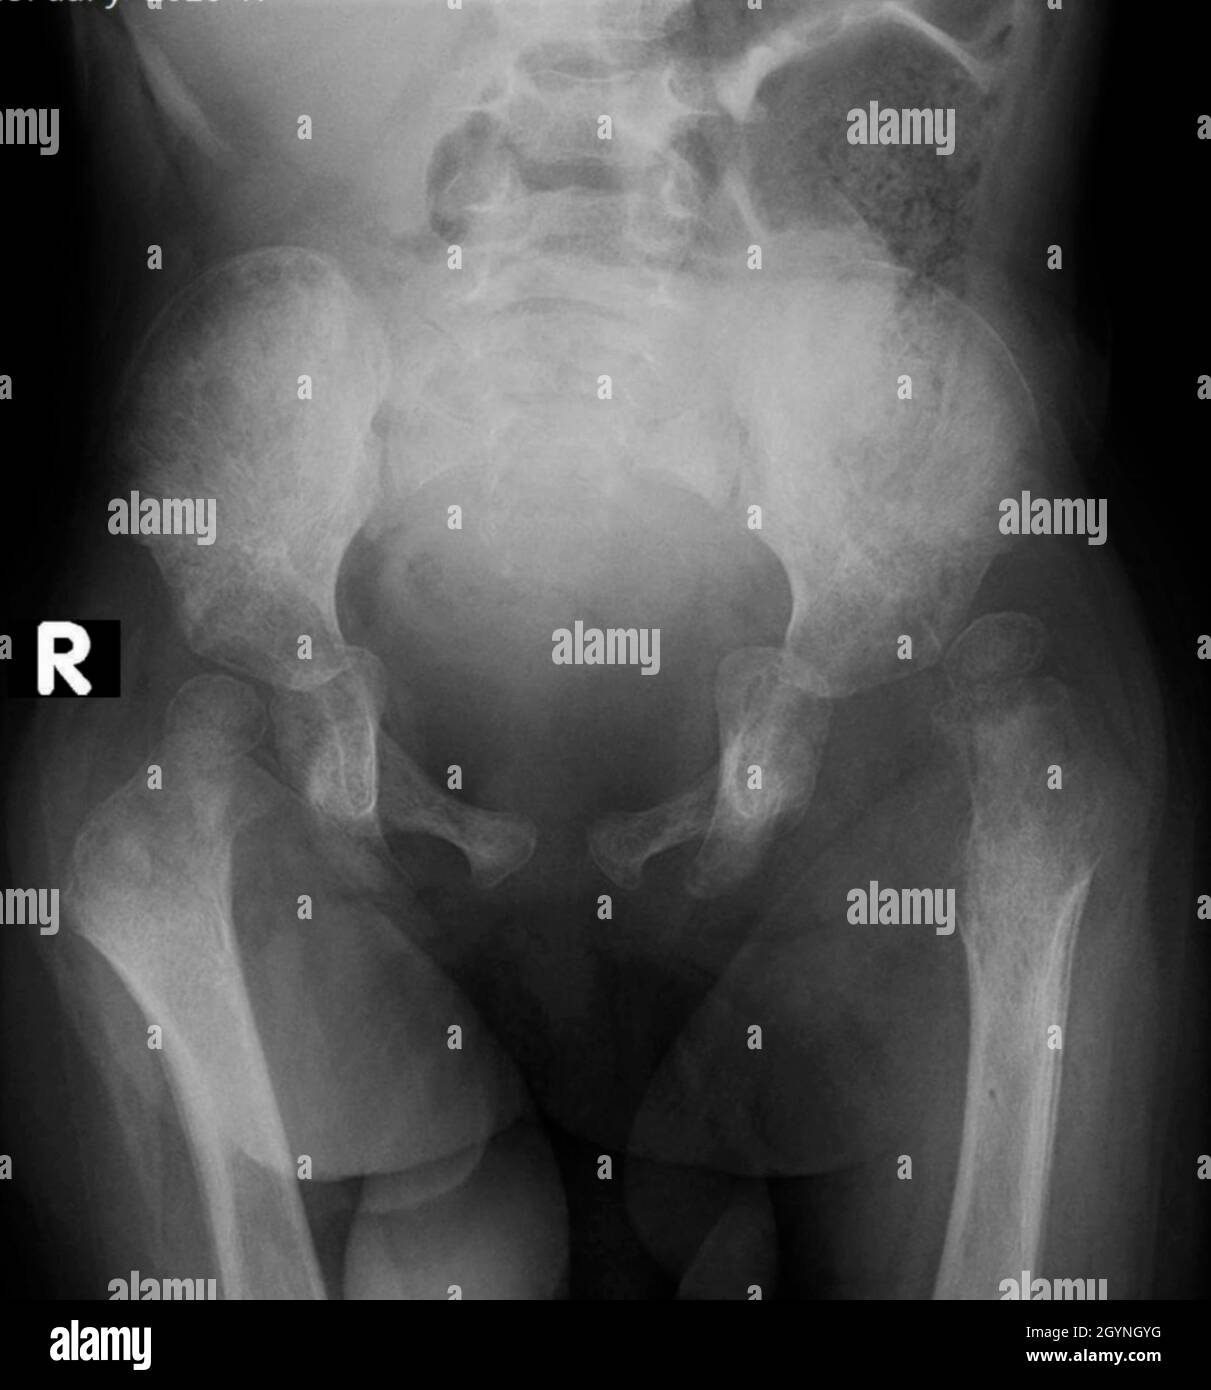

Radio dysplasie hanche bebe

Hanche luxée, hanche luxable, subluxation et dysplasie Les hanches luxées sont environ quatre fois moins fréquentes que les hanches luxables La LCH se constitue en général tardivement in utero lorsque les contraintes mécaniques sont maximales, avec un appui de la paroi utérine sur une hanche en « posture luxante » ; Le bébé possède encore une ossature très cartilagineuse non visible à la radiographie Dans le cas où les tests sont négatifs mais l'enfant présente des antécédents familiaux de dysplasie, alors, une échographie de contrôle sera demandée à 1 ou 4 moisLa radiographie du bassin de face a mis en évidence une dysplasie importante de hanche DROITE, c'estàdire un défaut d'architecture osseuse de la hanche (au niveau du bassin) Bien entendu, il n'y avait et il n'y a jamais eu aucun problème de dos Exemple de dysplasie de hanche droite sur une radiographie du bassin de face